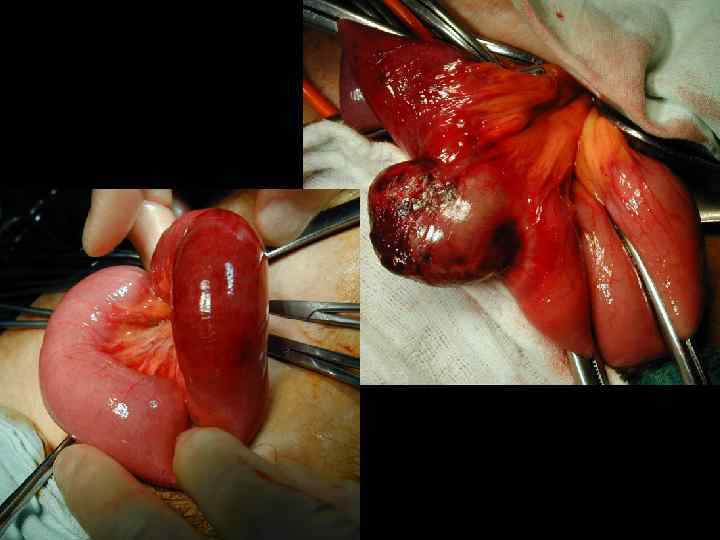

ЭТАПЫ ОПЕРАЦИИ ПРИ УЩЕМЛЕННОЙ ГРЫЖЕ • Рассечение кожи и подкожной клетчатки • Обнаружение дна грыжевого мешка без широкой мобилизации • Вскрытие грыжевого мешка • Фиксация ущемленного органа • Рассечение ущемляющего кольца • Оценка жизнеспособности ущемленных органов

ПРИЗНАКИ НЕЖИЗНЕСПОСОБНОСТИ КИШКИ • окраска – багровый или черный цвет • отсутствие пульсации краевых сосудов брыжейки • отсутствие перистальтики